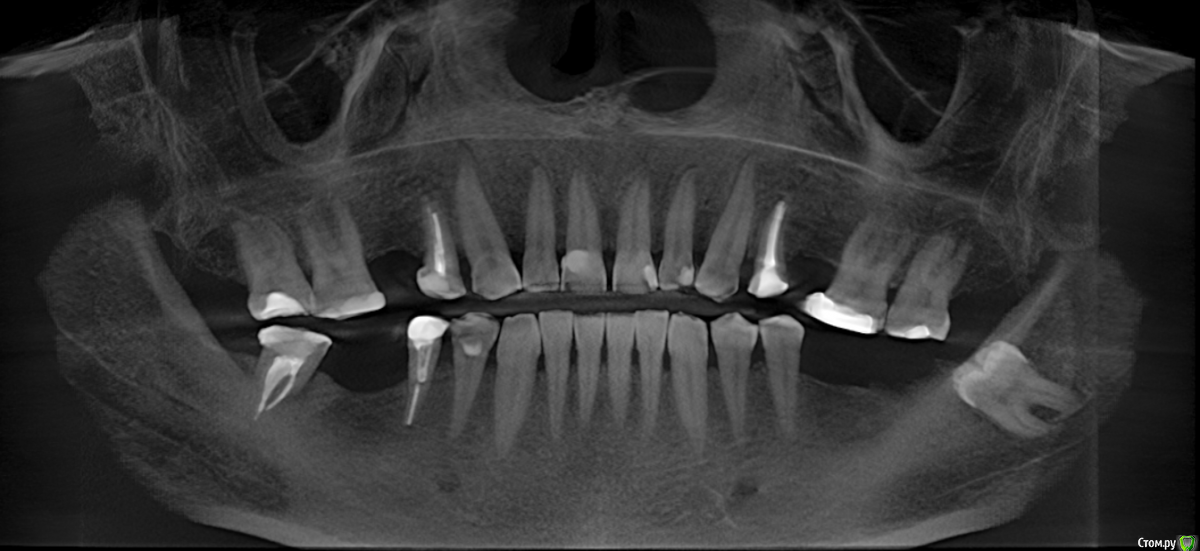

se77777 Опубликовано 9 декабря, 2019 Поделиться Опубликовано 9 декабря, 2019 (изменено) Добрый день, Для имплантации 36, 26,25 рекомендуют удалить опущенные 26, 27. 26 с "узлом".Пациенту 52 года. Возможно ли поднять 26 и 27 до необходимого для имплантации уровня и за какой срок это возможно сделать? фото улыбки и лица обещаю приложить позже. КТ https://yadi.sk/d/fcS6721v155x_Q С уважением,Сергей. Изменено 9 декабря, 2019 пользователем se77777 Ссылка на комментарий